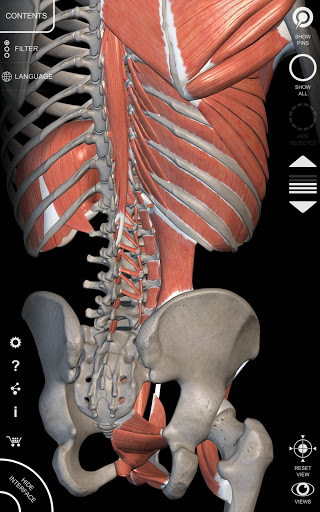

"Anatomy 3D Atlas" memungkinkan Anda mempelajari anatomi manusia dengan cara yang mudah dan interaktif.

Melalui antarmuka yang sederhana dan intuitif, Anda dapat mengamati setiap struktur anatomi dari sudut mana pun.

Model 3D anatomi sangat terperinci dan memiliki tekstur hingga resolusi 4k.

MODEL ANATOMI 3D

• Sistem muskuloskeletal

saraf • Sistem pernapasan • Sistem pencernaan • Sistem urogenital (pria dan wanita) • Sistem endokrin • Sistem limfatik • Sistem mata dan telinga FITUR • Antarmuka yang sederhana dan intuitif • Putar dan perbesar setiap model dalam ruang 3D • Opsi untuk menyembunyikan atau mengisolasi satu atau beberapa model yang dipilih • Filter untuk menyembunyikan atau menampilkan setiap sistem • Fungsi pencarian untuk menemukan setiap bagian anatomi dengan mudah • Fungsi penanda untuk menyimpan tampilan khusus • Rotasi cerdas yang menggerakkan pusat rotasi secara otomatis • Fungsi transparansi • Visualisasi otot melalui tingkat lapisan dari yang superfisial hingga yang terdalam • Dengan memilih model atau pin, istilah anatomi terkait akan muncul • Deskripsi otot: asal, • Tampilkan/ Sembunyikan antarmuka UI (sangat berguna dengan layar kecil) MULTIBAHASA • Istilah anatomi dan antarmuka pengguna tersedia dalam 11 bahasa: Latin, Inggris, Prancis, Jerman, Italia, Portugis, Turki, Rusia, Spanyol, Mandarin, Jepang, dan Korea • Istilah anatomi dapat ditampilkan dalam dua bahasa secara bersamaan PERSYARATAN SISTEM • Android 8.0 atau yang lebih baru, perangkat dengan RAM minimal 3GB Reversi